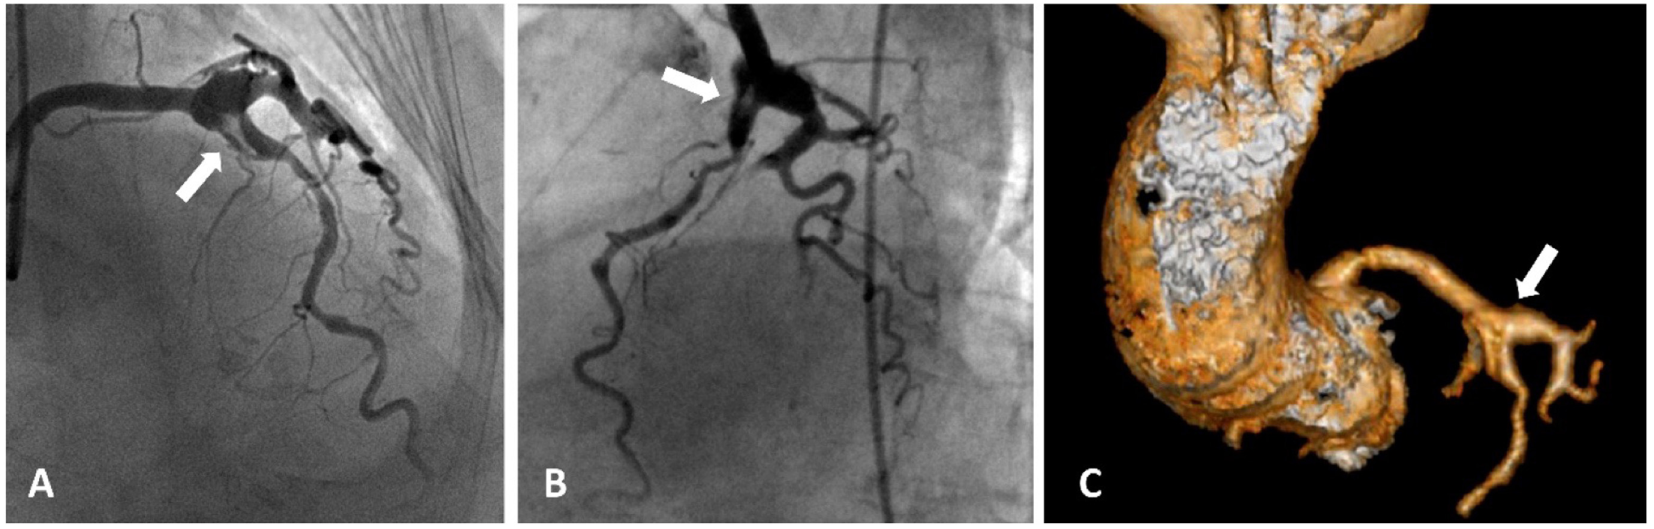

Figure 1

Acute coronary syndrome and coronary artery aneurysms. A patient presented with acute coronary aneurysm. (A,B) Coronary angiography revealed an aneurysmal dilatation of the ostia of the left anterior descending (LAD) artery and left circumflex artery, with a thrombus image (arrow heads) in the LAD artery along with a significant stenosis in the proximal part. Control angiogram failed to show any reduction in the thrombus after 48 h of tirofiban infusion, and the patient was referred to the surgery. (C) Aneurysmal dilatation can also be seen in computed tomography images.